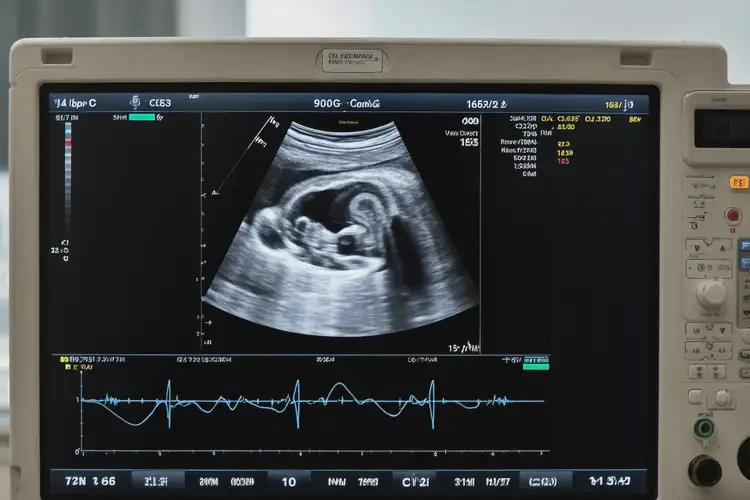

懷孕四個半月胎心165還能保住嗎(圖1)